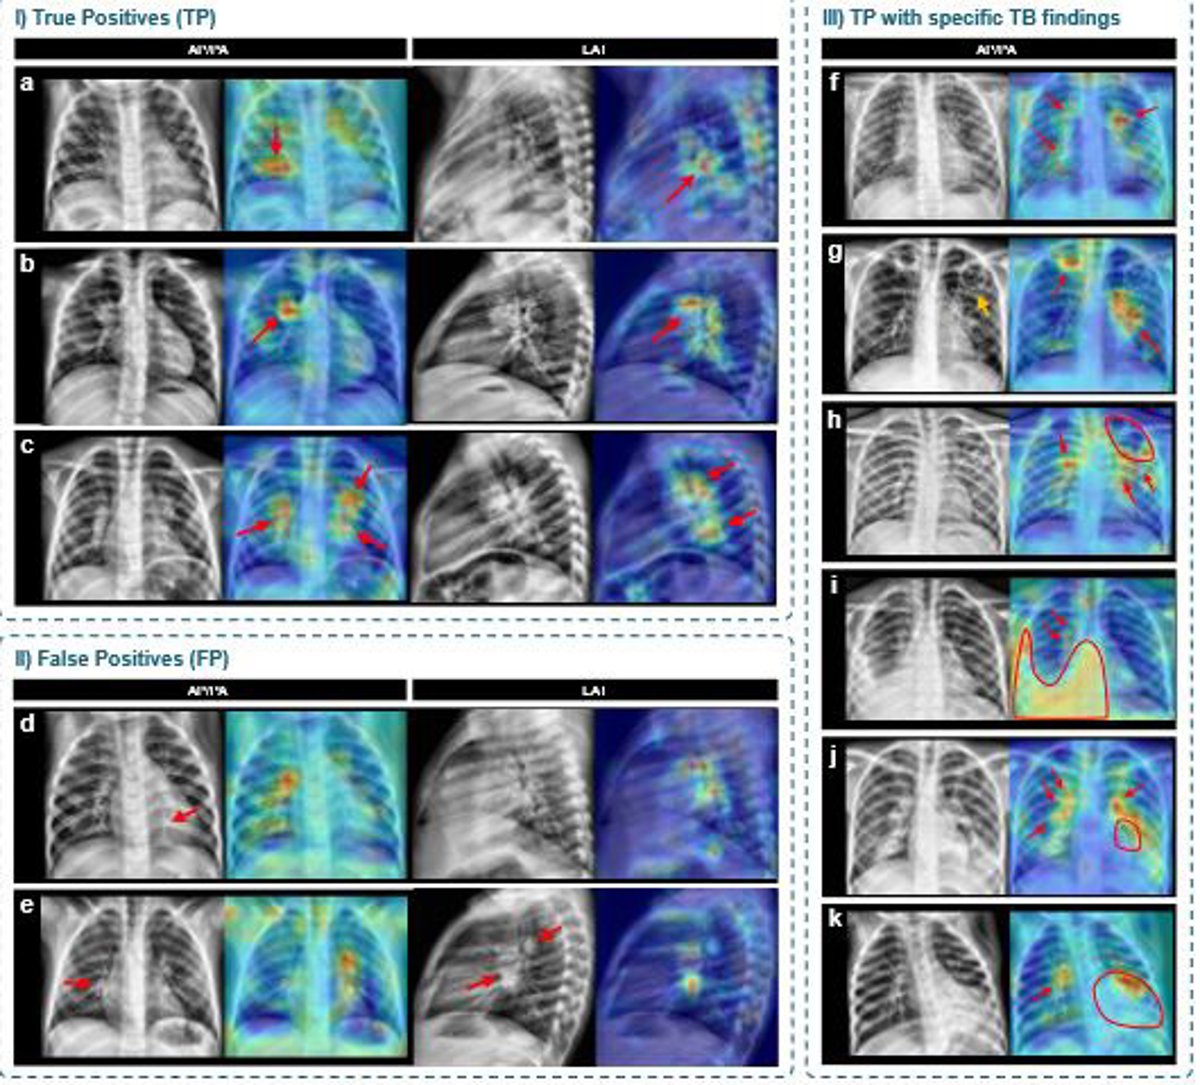

Mapas de activación generados mediante técnicas de explicabilidad que señalan las regiones de interés utilizadas por el modelo para tomar sus decisiones sobre las radiografías

Además de los resultados cuantitativos, el equipo incorporó técnicas de inteligencia artificial explicable que generan mapas visuales señalando las zonas de la radiografía que influyeron en cada decisión. Desde la UPC han subrayado que estas representaciones facilitan la revisión clínica de las predicciones y aumentan la confianza en el uso asistido por IA.